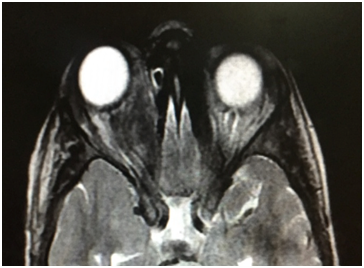

An orbital magnetic resonance imaging (MRI) revealed a well-defined cyst lesion sized 20×18×25 mm located in the intraconal space of the right orbit,hypointense on T1 weighted,hyper intense on T2 weighted, with marginal ring enhancement after an IV injection of gadolinium ethoxybenzyldiethylenetriaminepentaacetic(Figure 3).